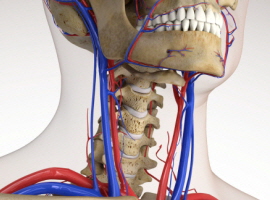

목디스크란 목뼈 사이에 있는 디스크가 손상되어 신경을 압박하는 질환을 의미합니다. 디스크는 젤리와 같은 수핵과 섬유륜으로 구성되어 있습니다. 섬유륜이 손상되면 수핵이 밖으로 밀려나와 신경을 압박하게 됩니다.

목디스크는 주로 잘못된 자세, 과도한 스트레스, 외상 등으로 발생합니다. 잘못된 자세로 장시간 컴퓨터를 사용하거나 운전을 하면 목에 무리가 가고 디스크가 손상될 수 있습니다.

또한 과도한 스트레스는 근육을 긴장시켜 디스크에 손상을 줄 수 있습니다. 외상은 교통사고, 운동 중 충격 등으로 목뼈가 부러지거나 골절되면 디스크가 손상될 수 있습니다.